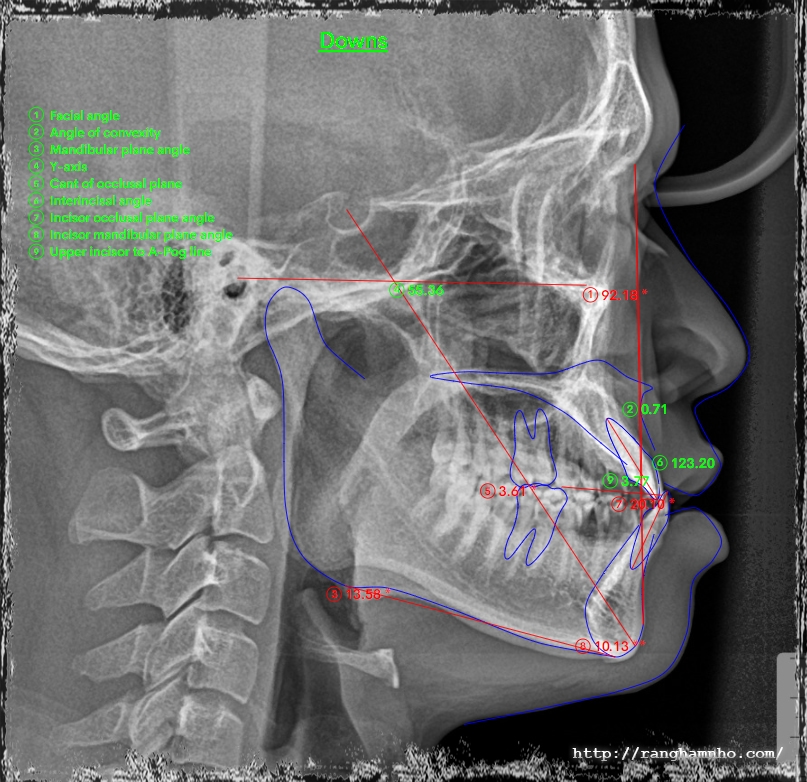

Cũng là khớp cắn ngược nhưng xét về độ khó thì khớp cắn ngược do răng điều trị sẽ đỡ vất vả hơn cắn ngược do xương nhiều. Bệnh nhân nam sinh năm 1998 đến khám niềng với mong muốn cải thiện nụ cười móm.

Kết quả tháo niềng sau 1.5 năm, thay đổi tích cực trên cả lâm sàng và trên phim xquang.